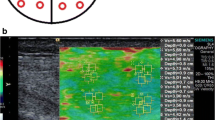

Two experienced readers (blinded to each other) independently scanned a single lesion per patient. Reader 1 (R1) was a board-qualified radiologist (author 4) with >18 years experience (>3 years with SWE). Reader 2 (R2) was a board-qualified sonographer (author 2) with 5 years experience (>2 years with SWE). Patients were placed in relaxed positions depending on the location of the lesion. Positions were adjusted to ensure no active (contraction) or passive (stretching) effects directly influenced the elasticity results. R1 marked the skin surface to determine transducer location and this was also used to place the probe by R2. Each reader made five measurements of shear wave velocity (m/s) and stiffness (kPa) in the transverse and craniocaudal (CC) planes from the most homogenously solid and vascularised region. The same region of the lesion was sampled each time. The probe was lightly replaced between each measurement using minimal probe pressure on the skin surface. Each reader defined the region of interest using a modifiable square box located in the most superficial aspect of the lesion that appeared solid (Fig. 1). Depth of measurement (cm) was recorded for each lesion and for each reader. Lesion volume (cm3) was also recorded for each lesion.

Both lesion depth and volume may potentially affect repeatability. To explore the impact of depth and volume further we proceeded to model the extent and variability of repeated measurements of transverse velocity as a function of measured lesion depth (cm) and volume (cm3). Separate models were constructed for each reader. To avoid over- or underestimating the association between variability and depth by including small numbers of observations at the extremes of the distribution, only lesions located between depths of 0.4 and 5 cm (61/64; 95%), were included in models.

The association between depth and measured velocity did not differ significantly between benign and malignant lesions for R1 (p = 0.358) or R2 (p = 0.261). The same was true for lesion volume (R1: p = 0.181; R2: p = 101). Combining benign and malignant lesions, on the log scale the difference in velocity per additional cm of depth (standard error) was −0.37 (0.08) for R1 (z = −4.85, p < 0.001) and −0.41 (0.07) for R2 (z = −5.88, p < 0.001) (Fig. 3). This equates to a decrease in velocity of approximately 3.5% for a 10% increase in depth. There was no evidence that measured velocity varied by depth for either reader (R1: p = 0.633; R2: p = 0.290).

The variability of shear-wave-velocity measurements in the transverse plane varied to a statistically significant degree according to both lesion depth and volume for both readers (all p < 0.01); however the direction of these trends varied between readers. For reader 1, variability increased with depth for lesions of all sizes, but the effect was most pronounced for the largest lesions. For reader 2, variability increased with depth for smaller lesions, but for the larger lesions variability decreased with depth.